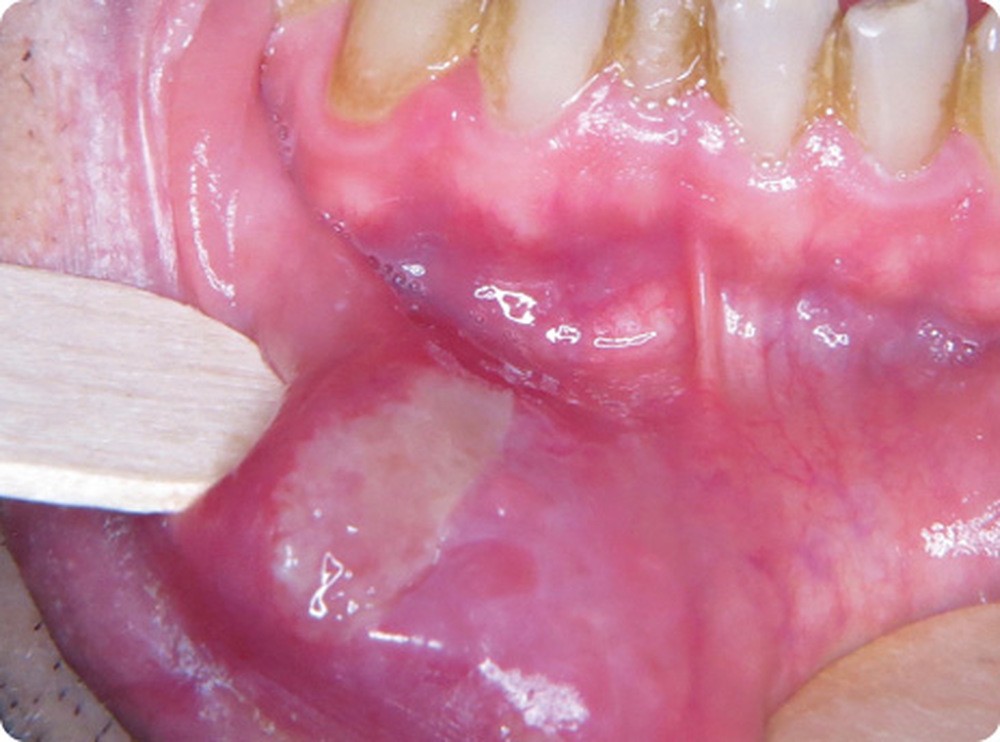

- Le patient présentait une ulcération de la partie muqueuse de la lèvre inférieure, latéralisée à droite. L’ulcération, de couleur jaunâtre, mesurait 1,5 cm par 3 cm. Les bords n’étaient pas surélevés et avaient une couleur rouge (inflammation) ou blanchâtre (œdème épithélial).